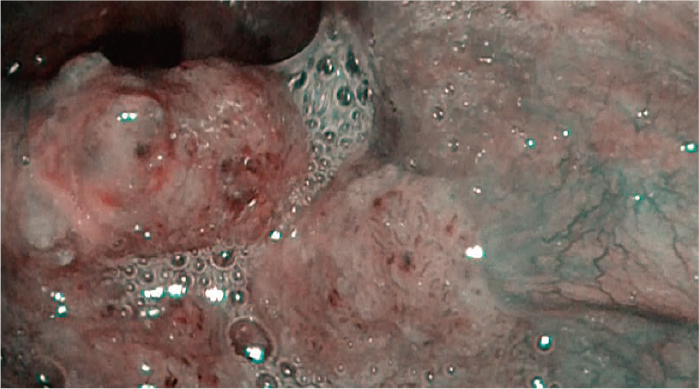

1耳鼻咽喉科内視鏡検査の進歩

耳鼻咽喉科内視鏡技術の進歩は近年著しい。Narrow Band Imaging(NBI)がもたらした早期癌の診断は、表在癌という新しい疾患概念を生み出した。咽喉頭癌の早期診断、低侵襲治療という新たな治療戦略で、日本が世界をリードしているが、これはひとえに内視鏡検査技術の開発、進歩によるところが大きい。今回内視鏡システムVISERA ELITE Ⅲとピストルグリップ形状の耳鼻咽喉ビデオスコープENF-VH2/V4(以下ピストルグリップENF)を用いて観察した早期癌の症例を提示し、その明るさや診断精度の高さについて紹介する。

この度、同一患者において、従来の内視鏡システム(VISERA ELITE)とVISERA ELITE Ⅲの静止画像を比較した。